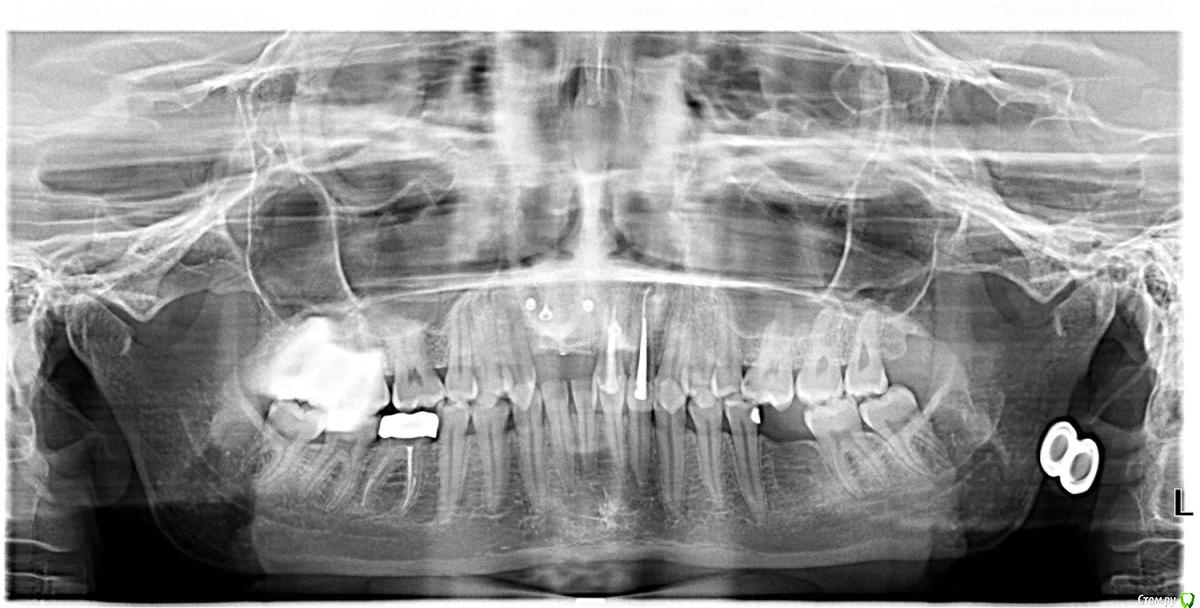

she-wo1f Опубликовано 16 сентября, 2017 Поделиться Опубликовано 16 сентября, 2017 Здравствуйте!Я планирую имплантацию 11, 12. В этой области уже была неудачная имплантация, подсадка кости и много других многолетних историй (не уверена, что подробности здесь нужны). 6ку снизу тоже буду имплантировать, но после передних.Ортопед, с которым консультировалась по поводу протезирования на будущих имплантах обратил мое внимание на неправильный прикус, и посоветовал проконсультироваться с ортодонтом, т.к. предположил возможность неправильной нагрузки на имплантированные резцы, и сопутствующие проблемы.Ортодонт по результатам осмотра и рентгена заключила, что исправление мне необходимо, и предложила брекеты на обе челюсти.Опыт знакомых и "людей из интернета" заставляет лишний раз задуматься действительно ли мне это необходимо.Меня не смущает эстетическая сторона вопроса и моя "неголливудская улыбка", хочется скорее привести зубы в умеренное состояние и забыть.Что бы вы посоветовали пациенту в моем случае?Достаточно ли брекетов в моем случае ? Читала, что в некоторых случаях требуется операция.Врач озвучила срок лечения брекетами - 1 год. Адекватная ли это цифра? Складывается впечатление, что в основном лечение занимает значительно больше времени.Возможны ли в моем случае альтернативы брекетам, например элайнеры? Ортодонт сказала одним из пунктов, что нужно выравнять направление верхних передних зубов, т.к. они сейчас "наружу". У меня оба резца под коронками... Есть ли смысл исправить направление коронковой части только переделав коронку и не исправлять это брекетами? Например, чтобы не травмировать лишний раз эти зубы.Есть ли какие-то риски при установке брекетов на коронки? Заранее благодарю за любые мнения! Ссылка на комментарий

she-wo1f Опубликовано 28 февраля, 2018 Автор Поделиться Опубликовано 28 февраля, 2018 (изменено) вновь доброго дня!вопрос в заголовке, пожалуй, не актуален. я решила, что хочу исправлять прикус. остается определиться со средствами. и, следовательно, такой вопрос:у меня передние верхние зубы полностью перекрывают нижние. + соприкасаются довольно плотно. в связи с этим, мне кажется, что брекеты на передних нижних зубах будут регулярно сдираться.похоже на реальную перспективу? + срезы КТhttps://drive.google.com/drive/folders/19I-XXNy0lLnsE3At-jksuy44a4sI9-w_?usp=sharing Изменено 28 февраля, 2018 пользователем she-wo1f Ссылка на комментарий